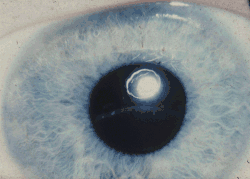

- zwichnięcie soczewki (ectopia lentis) jest niemal stałą cechą choroby u pacjentów powyżej 10. roku życia; występuje u 70% pacjentów młodszych niż 10 lat i u około 85% wszystkich chorych. Średnia wieku wystąpienia dyslokacji soczewki u nieleczonych pacjentów to 8 lat[54]. Występuje zazwyczaj wcześniej u chorych nieodpowiadających na leczenie niż u odpowiadających na leczenie pirydoksyną[55]. Bardzo rzadko obserwowano podwichnięcie soczewki w niemowlęctwie[56]. Powikłaniami dyslokacji soczewki są zez (24%), zaćma (21%), ostra jaskra (19%), odwarstwienie siatkówki (15%) i jednooczna ślepota (18%)